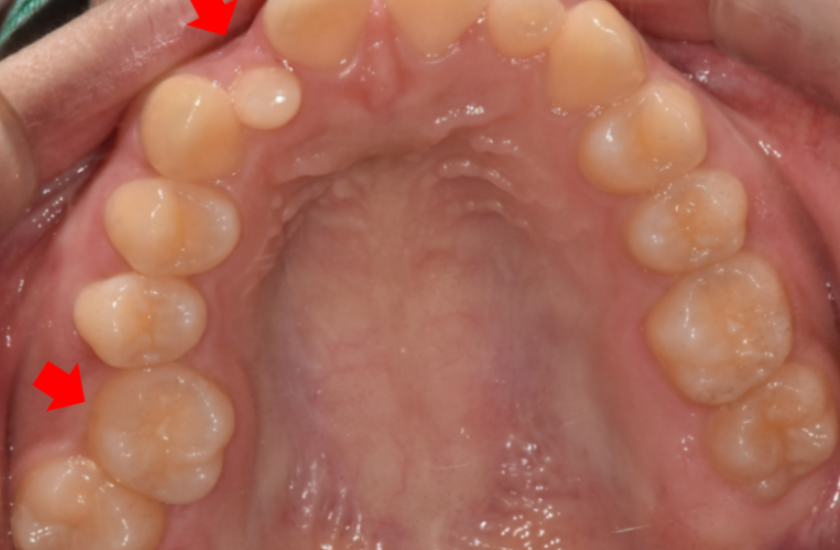

오늘 환자분도 왜소치로 내원을 해주셨는데

치아 배열이 전체적으로 교정이 필요했습니다.

교정을 통해 전체 치열을 가지런하게 정리하여

보철 치료가 들어갈 수 있는 기초 작업을 완성해야합니다.

교정으로 공간이 만들어지면

그때 왜소치 크기를 정상치와 비슷하게 맞추어 줍니다.